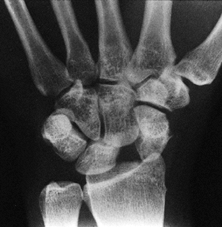

Consider reconstruction of a large or chronic scapholunate dissociation

Scapholunate gap of greater than 3 mm (Fig. 41.12)

Figure 41.12.

PA radiograph of the wrist showing a large scapholunate gap

representing a static scapholunate dislocation. It also shows that the

proximal pole of the scaphoid is trapped behind (i.e., dorsal or

posterior to) the radial styloid. This is sometimes described as a

scaphoid subluxation or dislocation, but the distal joint relationships

of the scaphoid are still reasonably intact. After the scaphoid is

reduced, treatment is carried out as for any other scapholunate

dissociation. -